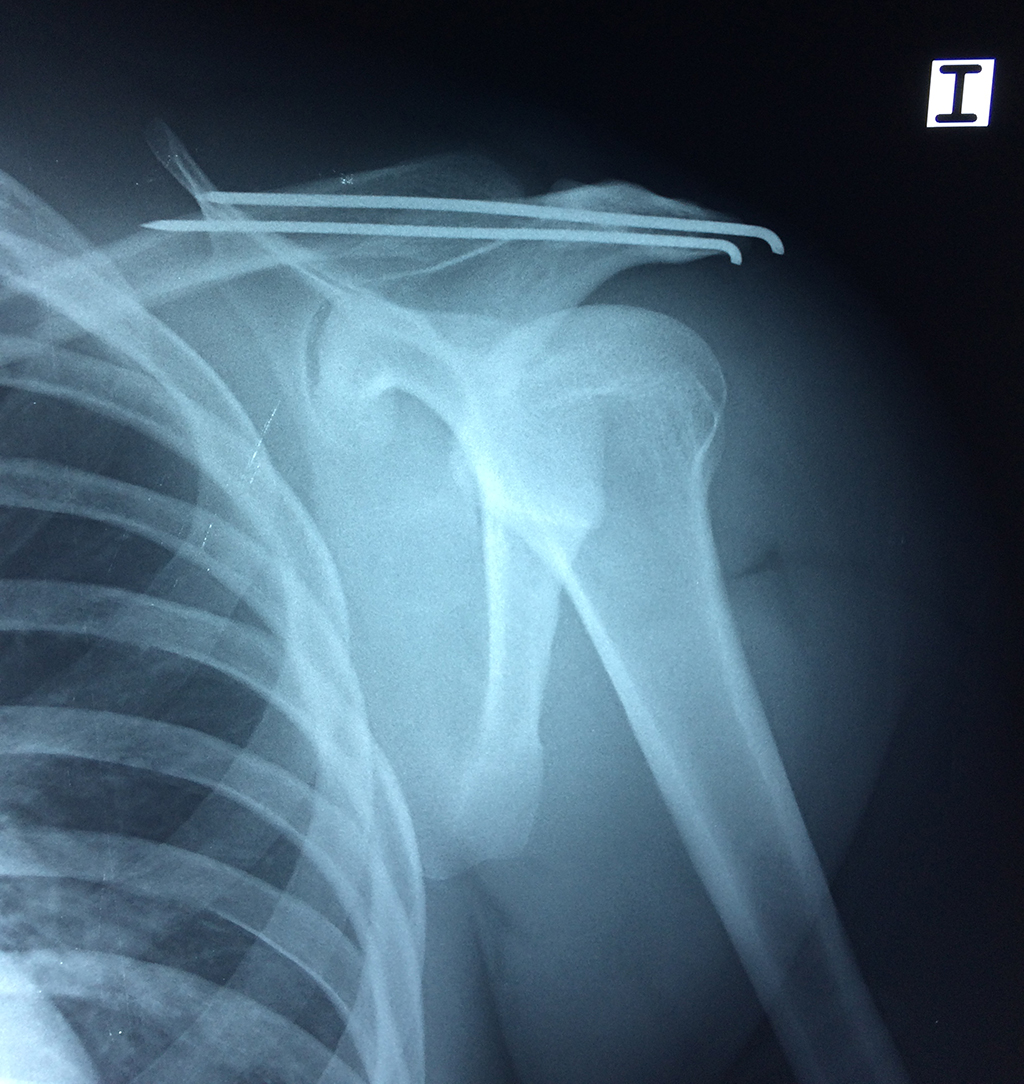

Exteriormente una envoltura de tejido blando circunda el conjunto, es la llamada cápsula articular que está reforzada por varios ligamentos que le dan estabilidad e impiden que los huesos se desplacen más allá de sus límites fisiológicos. Un conjunto de músculos y sus tendones se unen a las superficies de los huesos y hacen posible la movilidad de la articulación, entre ellos es muy importante el manguito rotador formado por cuatro músculos que proporcionan movilidad y estabilidad al hombro.